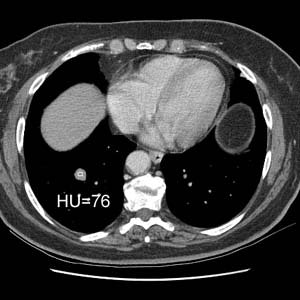

The lesion enhanced 52 HU after IV contrast administration which suggested a malignant lesion- it was removed and found to be an atypical carcinoid: